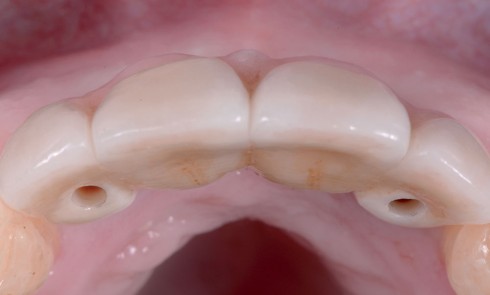

Article réservé à nos abonnés Prothèse amovible partielle combinée : à propos d’un cas clinique

L’apparition et la démocratisation de l’implantologie ont diminué les indications de PAP composite. Toutefois, dans certaines situations, conserver quelques dents...